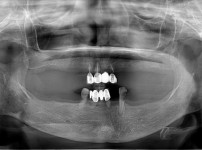

전악 임플란트

김OO님/치료기간:7개월/13개 식립